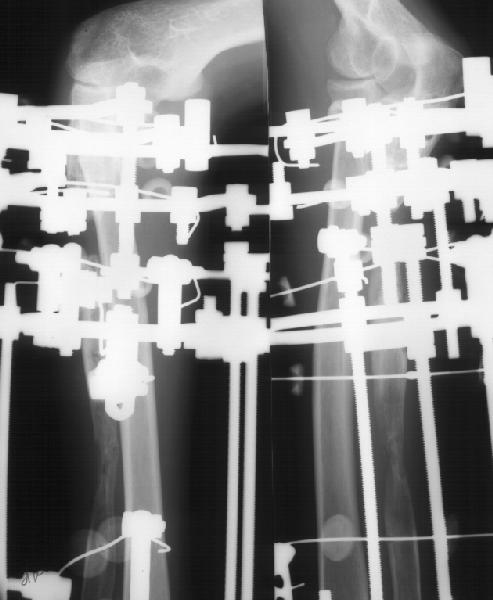

Мужчина 34 лет получил открытый перелом локтевой кости в апреле 1997 г. Через 2 недели - остеосинтез пластиной в местной больнице.Через 8 мес. пластика по Хахутову. В январе 2000 г. - аутопластика из крыла подвздошной кости. Трансплантат рассосался. С декабря 2001 г.наблюдается в институте. В январе 2002 г. - удаление пластинки, резекция концов отломков, остеотомия дистального отломка, дистракционный остеосинтез по Илизарову. Проводилась дистракция по 0,5 мм/сут., с перерывами на 10-14 дней.

Ввиду слабой регенерации темп уменьшен до 0,25 мм/сут. Дистракция закончена в июле 2002 г (см. приложение 1). Декабрьский снимок (приложение 2) показывает лизис концов отломков, замедленную перестройку регенерата.